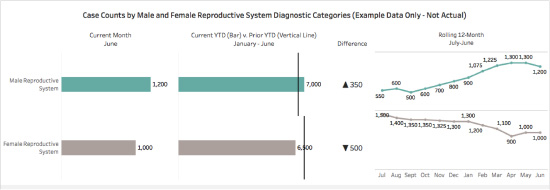

Imagine that we have been asked to create a display for a provider group that delivers services for patients (male and female) diagnosed with reproductive issues. The display needs to include the number of cases in each category for:

- the current month,

- the year to date compared with the previous year to date and the difference, and

- a twelve-month rolling trend.

For this example, let’s also assume that we are displaying data by calendar year, and that the last month of available data is for June of the current year.

Employing these techniques, we can use our label once and display the current month’s case count, followed by year-to-date versus prior year-to-date, and the 12-month rolling trend. Now the viewer can easily see that there are more cases for male than female in the current and year-to-date data, and that this seems to be an ongoing trend.